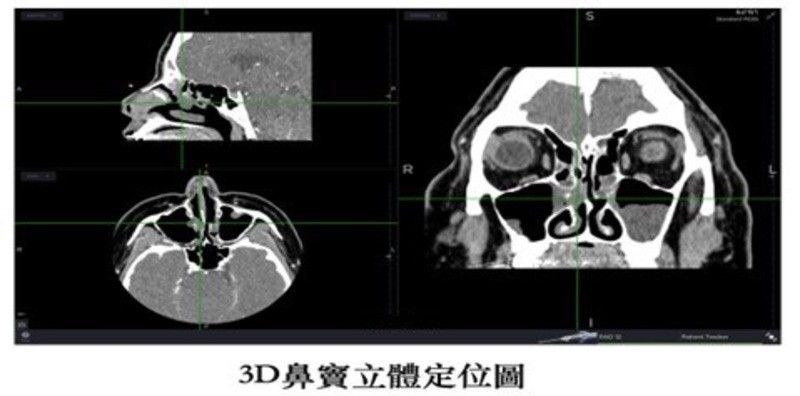

根據世界大型文獻統計,鼻竇炎手術一年內復發率為3.5%,5年內復發率為6.5%。人類的鼻竇極其複雜,過去醫師難以確定是否有將病灶完全清除乾淨。3D導航定位系統,利用光學或磁力定位,繪製出個人化的鼻竇圖形,清楚顯示病灶與正常鼻竇組織。原理是將電腦斷層影像上傳至導航系統,建立個人即時3D立體鼻竇影像,誤差範圍只有1~2mm。讓醫師在手術時精準移除病灶,確保眼睛跟顱部等中樞神經組織的安全性,提升治癒率。

另外,過去在處理較為深處的鼻竇如後篩竇、蝶竇及顱底部分,手術視野較為昏暗。高解析4K螢幕系統,相較於傳統HD系統,提升畫素、對比度及明亮度,對於神經與血管等重要組織,能夠看得更清楚,增加手術安全性。文獻顯示,病患術後在10年追縱下,生活品質獲得相當大的改善,顯示鼻竇手術治療的高成功率及術後效果。3D立體定位導航系統目前已納入健保給付範圍,患者不需要額外自費。